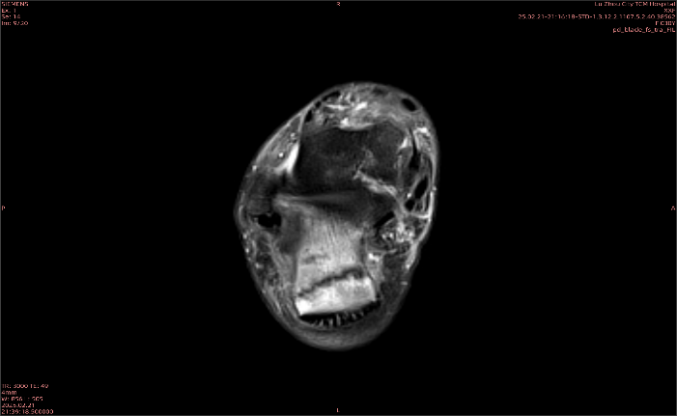

隱性骨折在MRI表現(xiàn)為T1WI序列上見由關(guān)節(jié)面向骨干走行的形態(tài)各異低信號區(qū),有線狀、條狀、紊亂低信號,信號強(qiáng)度不均勻。與T1WI低信號改變相對應(yīng)部位在T2WI上表現(xiàn)為相應(yīng)形狀的高、低混雜信號,且部分低信號周圍可見高信號水腫改變。STIR序列圖像上病灶呈顯著高信號,與信號被抑制的臨近正常骨髓形成鮮明對比,分界也較T2WI成像更為清楚。脂肪組織抑制技術(shù)是MRI的一個重要性能,脂肪抑制技術(shù)在MRI應(yīng)用中可以改善組織對比和增加病變顯示機(jī)會,這樣骨髓的脂肪抑制后就不會有任何信號,而隱性骨折線及骨髓水腫的異常高信號就會更加明顯的顯示出來。

舉例圖像

圖1

專業(yè)解釋看不懂沒關(guān)系,大家看圖1和圖2就可以了,這是同一個患者跟骨的磁共振和CT圖像,圖1的紅色箭頭指示的黑線就是磁共振圖像顯示的骨折線,一目了然。而對比圖2的CT圖像上并未顯示異常。